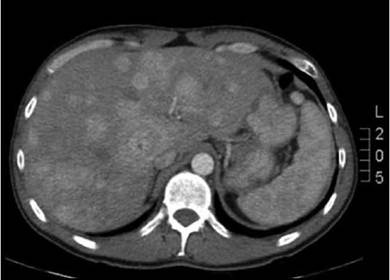

El diagnóstico se confirmó ante niveles muy elevados de cromogranina A (2499 ng/ml, VN: 0-100) y de 5-hidroxin-dolacético (5HIA) en orina (814 mg/24 horas, VN: 2-9), marcador específico de TNE productores de serotonina. En las pruebas de imagen se evidenciaron lesiones hepáticas múltiples ocupando el 30% de la glándula (Figura 1), captantes en el octreoscan (Figura 2). El resultado histopatológico fue metástasis de TNE con un Ki67<5% (compatible con bajo grado). El tumor primario se identificó mediante cápsula endoscópica en íleon medio y no existía más enfermedad a distancia en el estudio de extensión.